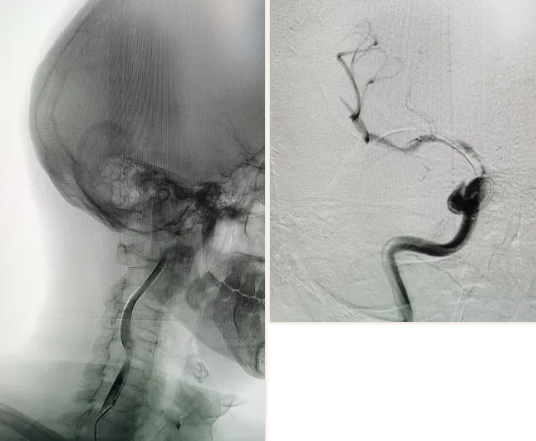

術(shù)前CT提示顱內(nèi)無出血性改變、MR圖像提示右側(cè)半球大面積缺血 ?

患者發(fā)病小于6小時(shí),經(jīng)急診、介入導(dǎo)管室和神經(jīng)內(nèi)科團(tuán)隊(duì)充分評估,患者存在可挽救的腦組織,可以進(jìn)行急診取栓治療。

顱內(nèi)動(dòng)脈取栓術(shù)是一項(xiàng)尖端的微創(chuàng)介入治療方法,指在數(shù)字減影血管造影技術(shù)(DSA)下,使用特殊裝置通過股動(dòng)脈到達(dá)顱內(nèi)動(dòng)脈血栓阻塞部位,直接通過取栓支架取栓、抽吸導(dǎo)管抽吸將堵塞的腦內(nèi)大動(dòng)脈中的血栓取出或抽出,使血流迅速再通,挽救缺血的腦組織。與過去傳統(tǒng)靜脈溶栓治療的方法相比,腦動(dòng)脈取栓技術(shù)急救“時(shí)間窗”更長,恢復(fù)率更高,將大大降低卒中患者的致殘率和死亡率,是一項(xiàng)安全、微創(chuàng)、有效的手術(shù)方式,目前已成為部分急性腦梗死患者首選的介入治療手段。